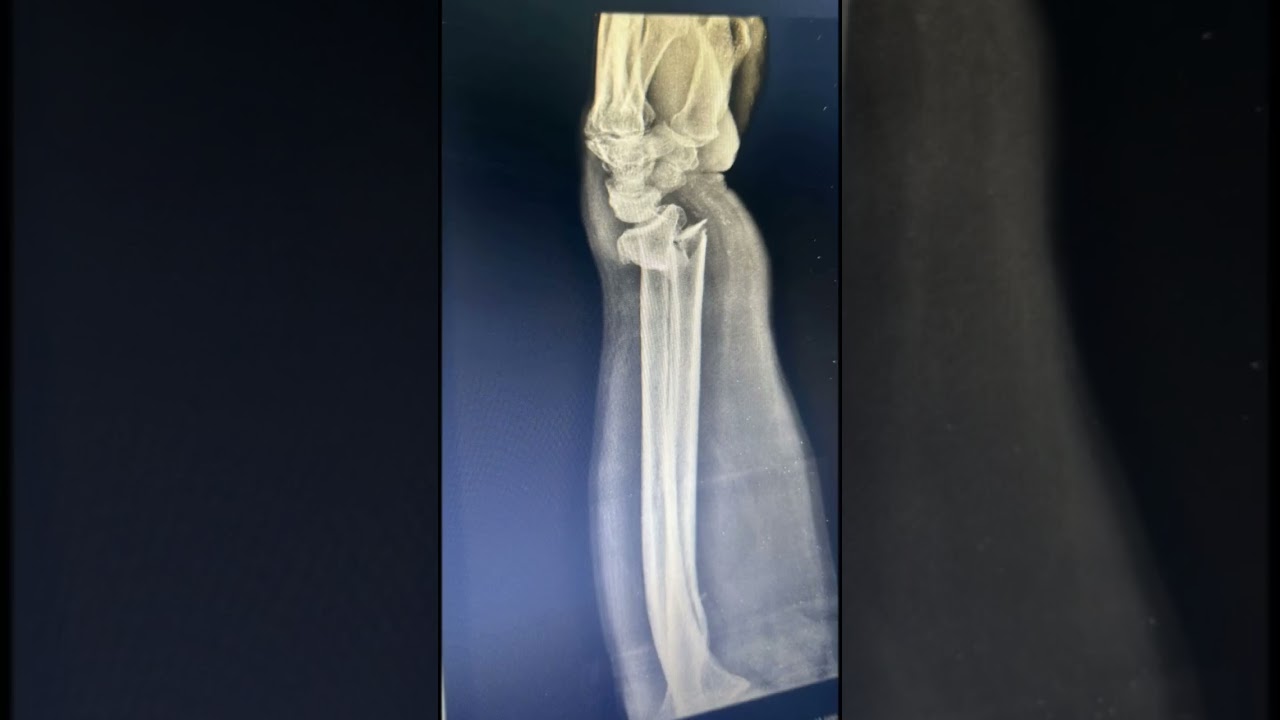

معرض الصور والفيدوهاتاضغط هنا لمشاهدة المزيد على قناتنا على YouTubeمعرض الصور والفيدوهات 8 Videos OrthoPro ندعوكم لأخذ جولة افتراضية للتعرف على عيادة 0:45 Subtrochanteric nonunion is treated by exchange nailing and ORIF 0:22 التهاب اللفافة الأخمصية: التشخيص والعلاج 0:50 Distal Radius Fracture treated by ORIF 0:25 Patella Fracture treated by ORIF 0:16 Lateral Condyle Fracture, treated by ORIF 0:13 نصائح لتقوية العظام 0:27 Deformity Correction Workshop by Orthofix 0:15